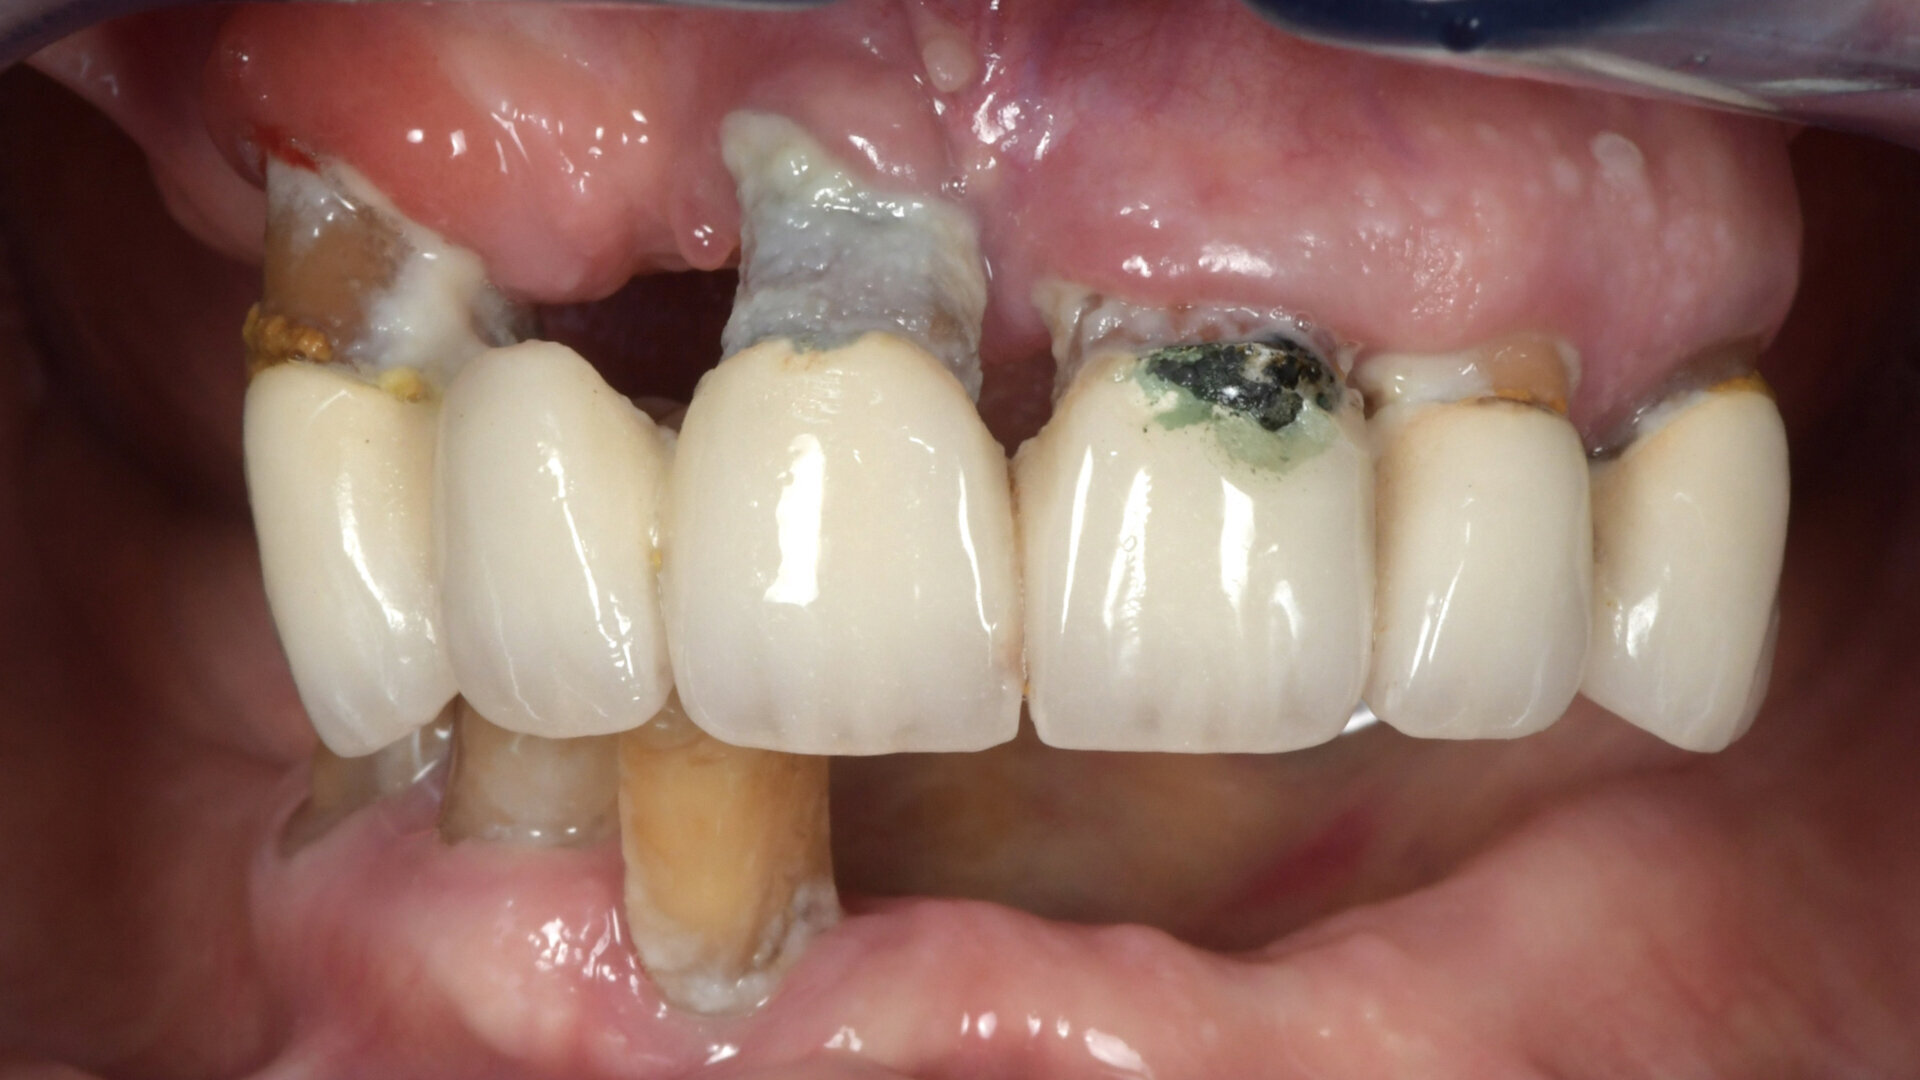

Fig. 2 : Vue intra-buccale du bridge maxillaire (avec d’importantes récessions) et des trois dents mandibulaires résiduelles.

L’évaluation clinique a révélé un manque de soutien dentaire pour la lèvre inférieure et une récession gingivale significative autour du bridge maxillaire et des trois dents mandibulaires résiduelles (Figs. 1 et 2). Après examen clinique et radiologique (Figs. 3 et 4), la décision de réalisation d’une prothèse complète maxillaire et d’une réhabilitation fixe mandibulaire par implants est prise en accord avec la patiente.